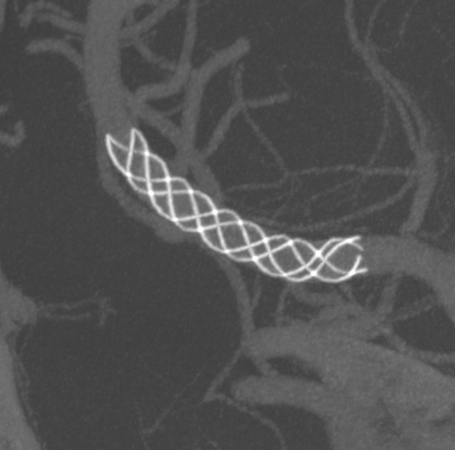

畅医达(Accessway)0.017支架微导管在0.014微导丝引导下顺利到达右侧大脑中动脉M2远端,经支架微导管引入畅医达(Choydar)血流导向装置,3mm*15mm,推送平顺,然后跨瘤颈缓慢释放支架,支架头端打开良好。

支架部分释放后复查造影示支架位置良好,缓慢完全释放支架,支架打开良好,复查造影示支架位置良好,完全覆盖瘤颈,贴壁佳,瘤囊内可见造影剂滞留明显,OKM分级A3。

Vaso CT显示 畅医达(Choydar)血流导向装置 位置良好,完全覆盖瘤颈,长轴及横轴薄层均显示支架贴壁良好。